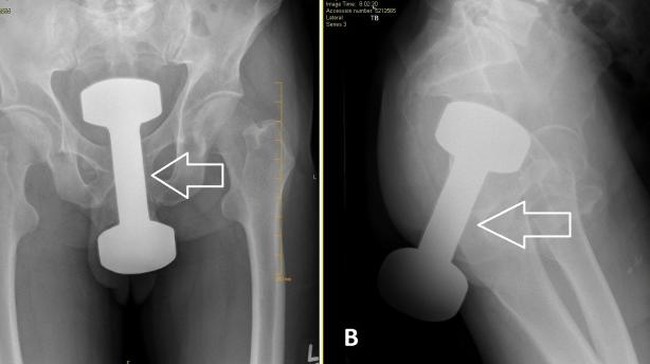

Dumbell dalam anus. Foto: Cureus Journal

Hasil pemeriksaan medis menunjukkan ada dumbell gym seberat 5 pon atau sekitar 2,2 kilogram tertahan di dalam rektumnya. Catatan medis pasien tidak memperlihatkan adanya riwayat penyakit yang mengkhawatirkan.

"Radiografi abdomen biplanar memperlihatkan adanya bayangan benda asing radiodense di garis tengah panggul yang konsisten dengan riwayat adanya dumbell lima pon. Tim bedah kemudian dikonsultasikan," lanjut laporan tersebut.